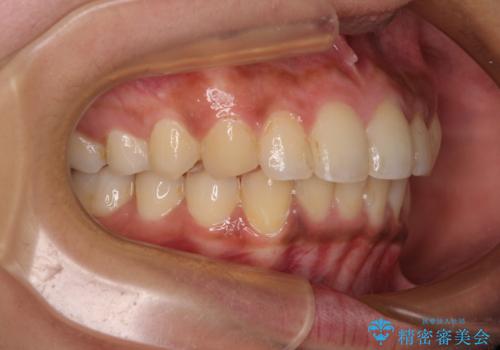

深い咬み合わせと前歯のデコボコ インビザラインによる矯正治療

- 前歯のデコボコと、食いしばりやすい咬み合わせを気にして来院された患者様です。

骨格的に下顎骨が左側に偏位しており、インビザラインでの矯正治療では奥歯の咬みにくさが残る仕上がりが懸念されましたが、新幹線での通院となるため、来院回数の少ないインビザラインでの治療を希望されました。

リスクをご説明した上で、インビザラインにより気になっている叢生と深い咬み合わせを改善していくこととしました。

治療途中では、左右ともに奥歯が咬みにくい状態が続き、問題なく噛めるようになるまでに長期間を要しました。

一方で、デコボコや下顎の前歯が隠れてしまうほどの深い咬み合わせはしっかりと改善されました。